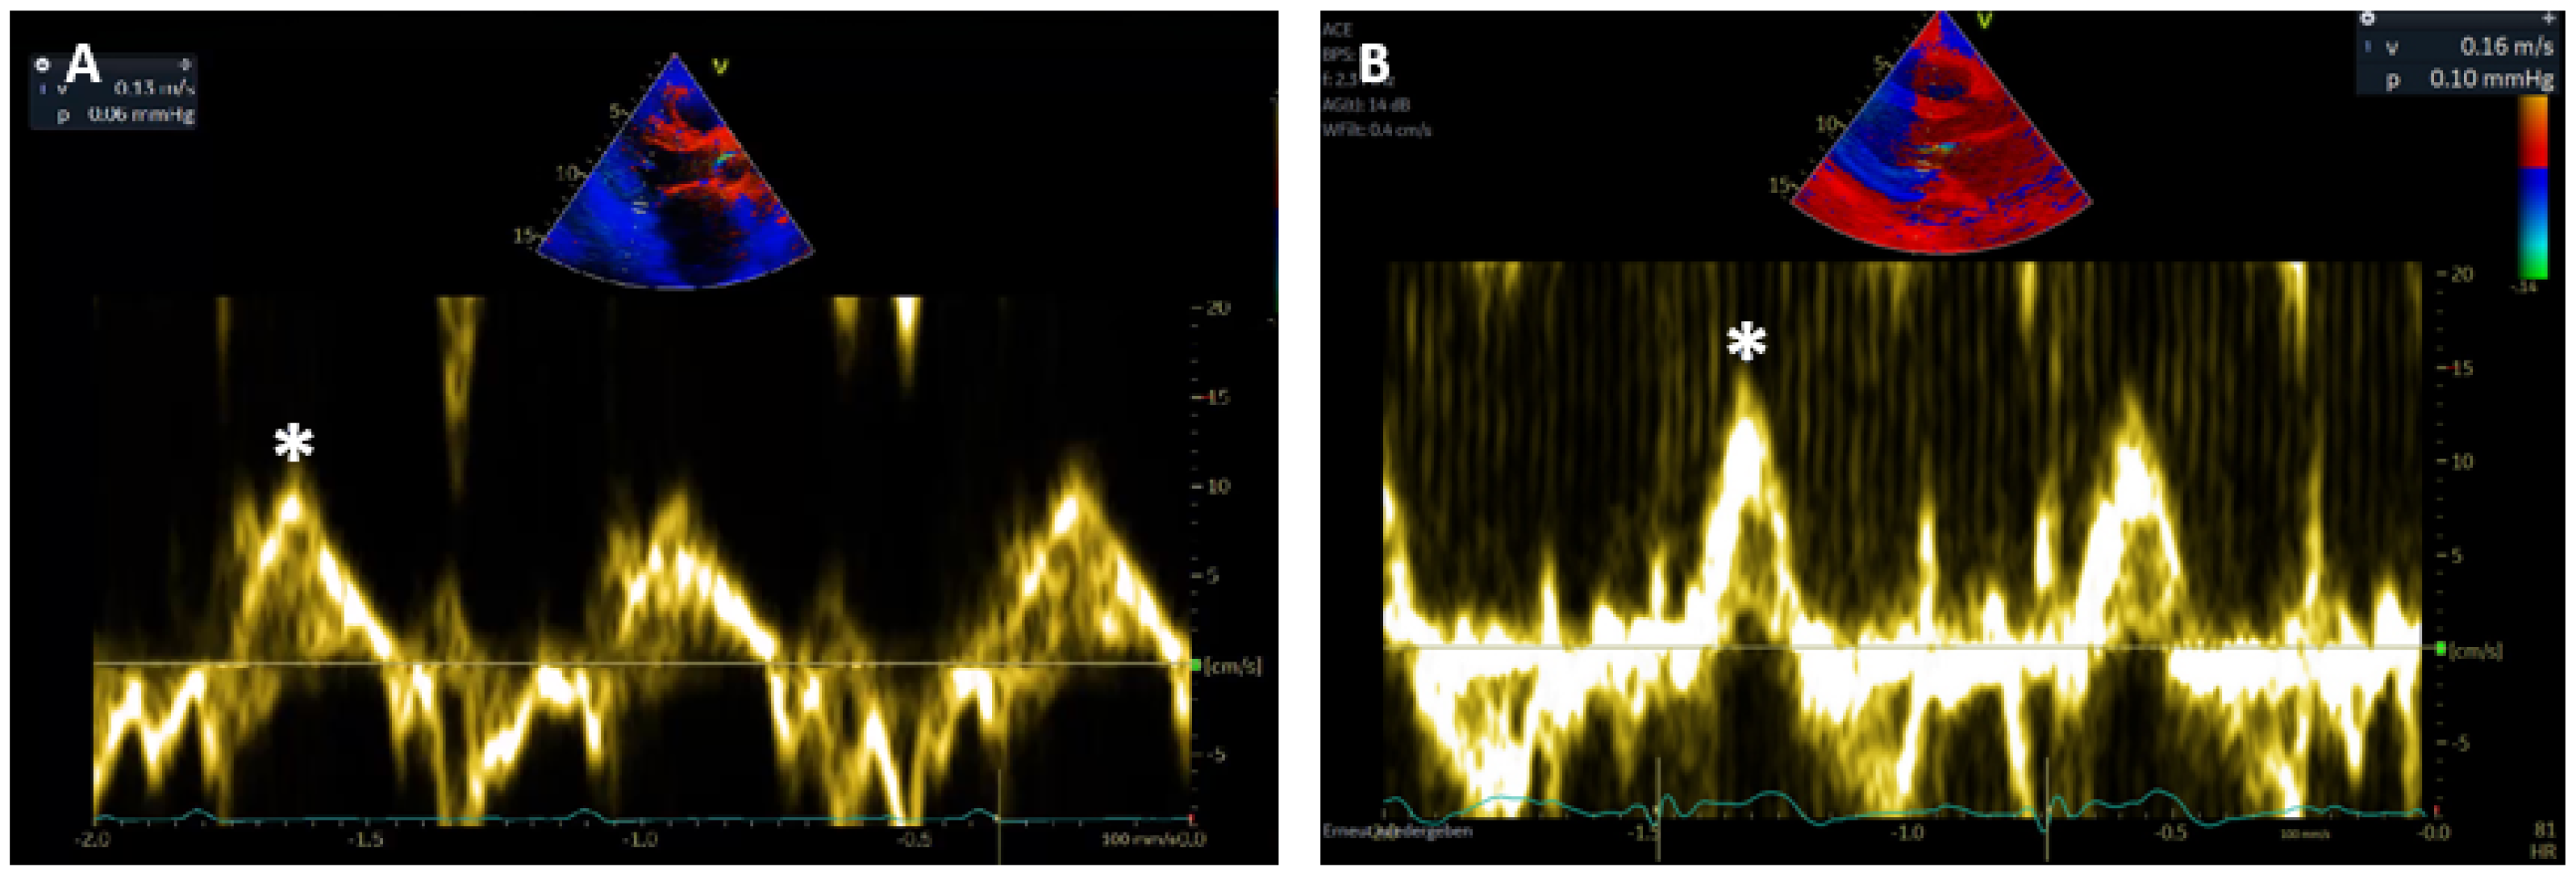

Systolic wall motion peak velocities (Sm) were measured by PW-TDI at the subendocardial, posterobasal segment of the left ventricle at the level of the mitral leaflet tips. Radial wall motion was measured in parasternal long axis view and longitudinal wall motion in apical 3-chamber view [12]. In routine echocardiography, measurements of the Sm during or after extrasystoles are excluded from analysis. Since transducer angulation might result in a detection of lower velocities, the highest systolic wall motion velocity from at least three beats was selected in clinical routine (Figure 2).

Figure 2. (A) Longitudinal and (B) radial Sm measured by PW-TDI at basal posterolateral segment of the LV (*).